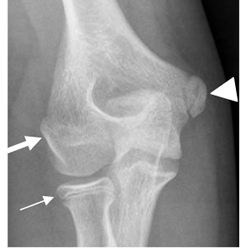

Fig 37 A. Avulsión del codo.

Rx AP. Avulsión no desplazada, del epicóndilo medial.

Fig 37 B. Avulsión del codo.

Rx AP. Desplazamiento inferior del núcleo de crecimiento, del epicóndilo medial.